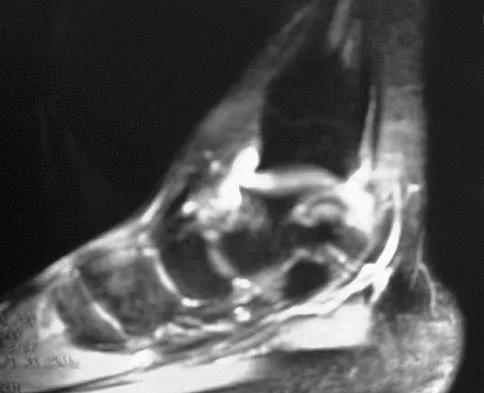

Question 37

Figure 7 shows the MRI scan of a 23-year-old competitive rugby player who has anterior ankle pain and swelling. He states that he has been playing for many years and has sprained his ankle several times. Examination will reveal what specific hallmark feature?

Explanation